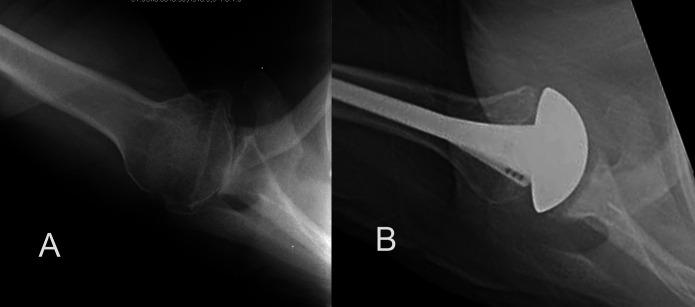

This study evaluated the ability of shoulder arthroplasty using a standard glenoid component to improve patient self-assessed comfort and function and to correct preoperative humeral-head decentering on the face of the glenoid in patients with primary glenohumeral arthritis and type-B2 or B3 glenoids.

We identified 66 shoulders with type-B2 glenoids (n = 40) or type-B3 glenoids (n = 26) undergoing total shoulder arthroplasties with a non-augmented glenoid component inserted without attempting to normalize glenoid version and with clinical and radiographic follow-up that was a minimum of 2 years. The Simple Shoulder Test (SST), the percentage of humeral-head decentering on the glenoid face, and bone ingrowth into the central peg were the main outcome variables of interest. Similar analyses were made for concurrent patients with type-A1, A2, B1, and D glenoid pathoanatomy to determine if the outcomes for type-B2 and B3 glenoids were inferior to those for the other types.

The SST score (and standard deviation) improved from 3.2 ± 2.1 points preoperatively to 9.9 ± 2.4 points postoperatively (p < 0.001) at a mean time of 2.8 ± 1.2 years for type-B2 glenoids and from 3.0 ± 2.5 points preoperatively to 9.4 ± 2.1 points postoperatively (p < 0.001) at a mean time of 2.9 ± 1.5 years for type-B3 glenoids; these results were not inferior to those for shoulders with other glenoid types. Postoperative glenoid version was not significantly different (p > 0.05) from preoperative glenoid version. The mean humeral-head decentering on the glenoid face was reduced for type-B2 glenoids from -14% ± 7% preoperatively to -1% ± 2% postoperatively (p < 0.001) and for type-B3 glenoids from -4% ± 6% preoperatively to -1% ± 3% postoperatively (p = 0.027). The rates of bone integration into the central peg for type-B2 glenoids (83%) and type-B3 glenoids (81%) were not inferior to those for other glenoid types.

Shoulder arthroplasty with a standard glenoid inserted without changing version can significantly improve patient comfort and function and consistently center the humeral head on the glenoid face in shoulders with type-B2 and B3 glenoids, achieving >80% osseous integration into the central peg. These clinical and radiographic outcomes for type-B2 and B3 glenoids were not inferior to those outcomes for other glenoid types.

本研究评估了在原发性盂肱关节炎且为B2型或B3型肩胛盂的患者中,使用标准肩胛盂假体进行肩关节置换术改善患者自我评估的舒适度和功能,以及纠正术前肱骨头在肩胛盂表面偏心的能力。

我们确定了66例接受全肩关节置换术的肩胛盂,其中40例为B2型肩胛盂,26例为B3型肩胛盂,植入非增强型肩胛盂假体时未试图使肩胛盂角度正常化,临床和影像学随访至少2年。简易肩关节测试(SST)、肱骨头在肩胛盂表面的偏心百分比以及骨长入中心栓是主要关注的结局变量。对同时患有A1型、A2型、B1型和D型肩胛盂病理解剖的患者进行了类似分析,以确定B2型和B3型肩胛盂的结局是否劣于其他类型。

对于B2型肩胛盂,在平均2.8±1.2年时,SST评分(及标准差)从术前的3.2±2.1分提高到术后的9.9±2.4分(p<0.001);对于B3型肩胛盂,在平均2.9±1.5年时,SST评分从术前的3.0±2.5分提高到术后的9.4±2.1分(p<0.001);这些结果并不劣于其他肩胛盂类型的肩关节。术后肩胛盂角度与术前相比无显著差异(p>0.05)。B2型肩胛盂肱骨头在肩胛盂表面的平均偏心度从术前的-14%±7%降至术后的-1%±2%(p<0.001),B3型肩胛盂从术前的-4%±6%降至术后的-1%±3%(p=0.027)。B2型肩胛盂(83%)和B3型肩胛盂(81%)骨长入中心栓的比例不低于其他肩胛盂类型。

植入标准肩胛盂且不改变角度的肩关节置换术可显著改善患者舒适度和功能,并持续使B2型和B3型肩胛盂肩关节的肱骨头在肩胛盂表面居中,实现中心栓骨整合率>80%。B2型和B3型肩胛盂的这些临床和影像学结局并不劣于其他肩胛盂类型。